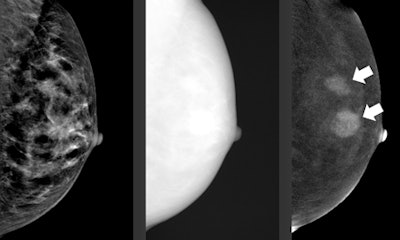

He plans to provide an overview for both dedicated and general radiologists of the current most promising developments, including contrast-enhanced mammography, also called contrast-enhanced spectral mammography (CESM), which became commercially available in 2011. It uses an iodine-based contrast agent and a dual-energy technique to increase the diagnostic accuracy of mammography.

"In recent years, many studies have shown that CESM is consistently superior to full-field digital mammography [FFDM] in breast cancer detection and able to achieve results similar to breast MRI, which is still considered to be the most accurate breast cancer detection modality," Lobbes noted.

CESM could easily be implemented in everyday clinical practice, but there are some disadvantages, such as the use of iodine-based contrast agents and the 80% increase in radiation dose. Also, CESM doesn't have proper indications, he added.

"Although it is superior to FFDM and the principle is similar to that of breast MRI, proper indications are still lacking," he stated. "Nonetheless, many studies are currently ongoing to clarify the strengths and weaknesses of CESM, so it is safe to assume that more knowledge on CESM indications will be gathered in the next few years."